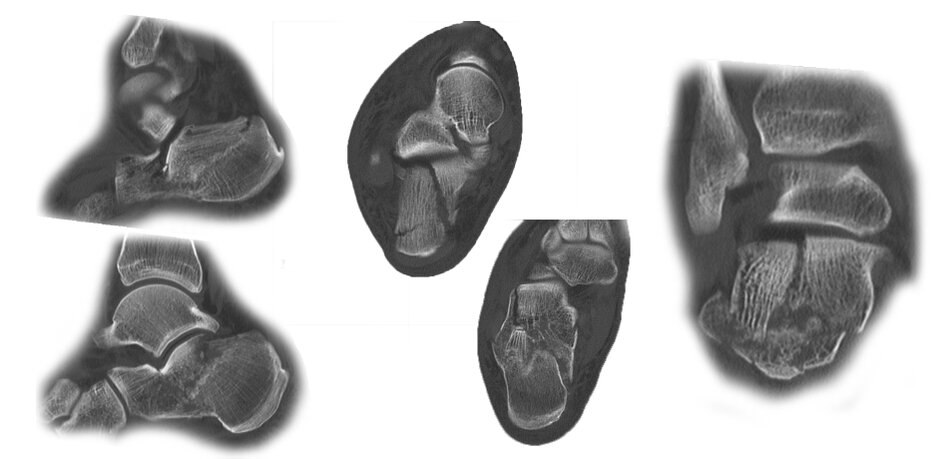

Case 17KL, male, 35y, surgery on day of trauma